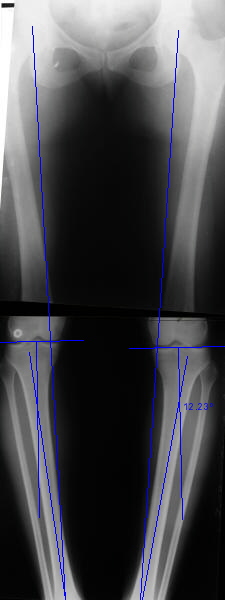

Вот, с учетом и без учета, и на разных уровнях...

AC> Вот, с учетом и без учета, и на разных уровнях...

AC> Саша Артемьев, может, для данного случая свой вариант нарисуешь?

Из приведнной схемы не совсеим понял что означают разноцветные линии.

И зачем латерализация периферического фрагмента. Я всегда делаю медиализацию. См схему. И для данного случая медиализация подходит как нельзя лучше.

a> Из приведнной схемы не совсеим понял что означают разноцветные линии.

Черные - это нынешняя механическая ось. Красные - это планируемая правильная ось.

a> И зачем латерализация периферического фрагмента.

;-) Читайте Палея. Стр. 114-115.

a> Я всегда делаю медиализацию. См схему. И для данного случая

Медиализация - это чисто эстетический прием, как я понимаю. Поскольку если делать остеотомию ниже вершины деформации, для восстановления оси надо делать смещение по ширине, в данном случае как раз латерализацию.

А вот на схемке без осей - там на разных уровнях (который правильнее?) устранение варуса чисто открытым клином без медиализации-латерализации. Если как-то так сделать - этого недостаточно будет?